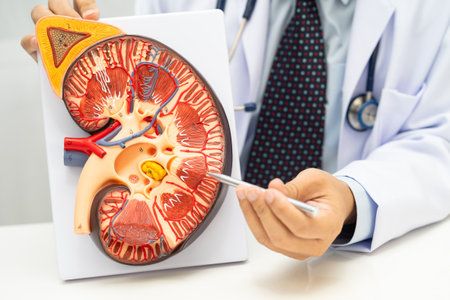

Chronic kidney disease, doctor with model for treatment urinary system, urology, Estimated glomerular filtration rate eGFR.

Chronic kidney disease, doctor with model for treatment urinary system, urology, Estimated glomerular filtration rate eGFR.

Doctor examines renal model while holding a medication strip in a clinical setting for educational purposes

Kidney disease, Chronic kidney disease ckd, Doctor hold human model to treat and study in hospital.

Chronic kidney disease, doctor holding model for treatment urinary system, urology, Estimated glomerular filtration rate eGFR.

Chronic kidney disease, doctor with model for treatment urinary system, urology, Estimated glomerular filtration rate eGFR.

Human Kidney Model with Chronic Kidney Disease Damage Held by Doctor

Chronic kidney disease, Asian woman with model for treatment urinary system, urology, Estimated glomerular filtration rate eGFR.

Kidney disease, Chronic kidney disease ckd, Doctor hold human model to treat and study in hospital.

Chronic kidney disease, doctor holding model for treatment urinary system, urology, Estimated glomerular filtration rate eGFR.

Chronic kidney disease, doctor holding model for treatment urinary system, urology, Estimated glomerular filtration rate eGFR.

Kidney disease, Chronic kidney disease ckd, Doctor with human model to study and treat in hospital.